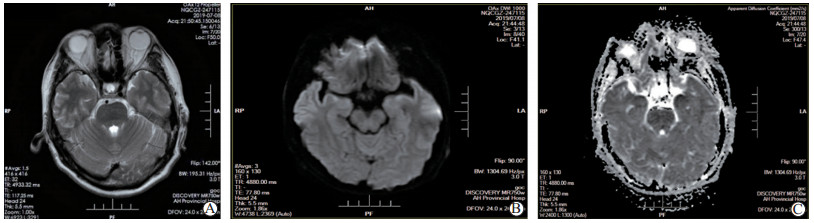

肝移植术后人疱疹病毒6B型脑炎的多学科综合诊疗

郭亚飞, 王继洲, 朱泽斌, 陈翠, 刘国岩, 群森, 邓克学, 黄德好, 刘连新

2021, 12(4): 465-471. DOI: 10.3969/j.issn.1674-7445.2021.04.014

摘要 HTML全文 PDF